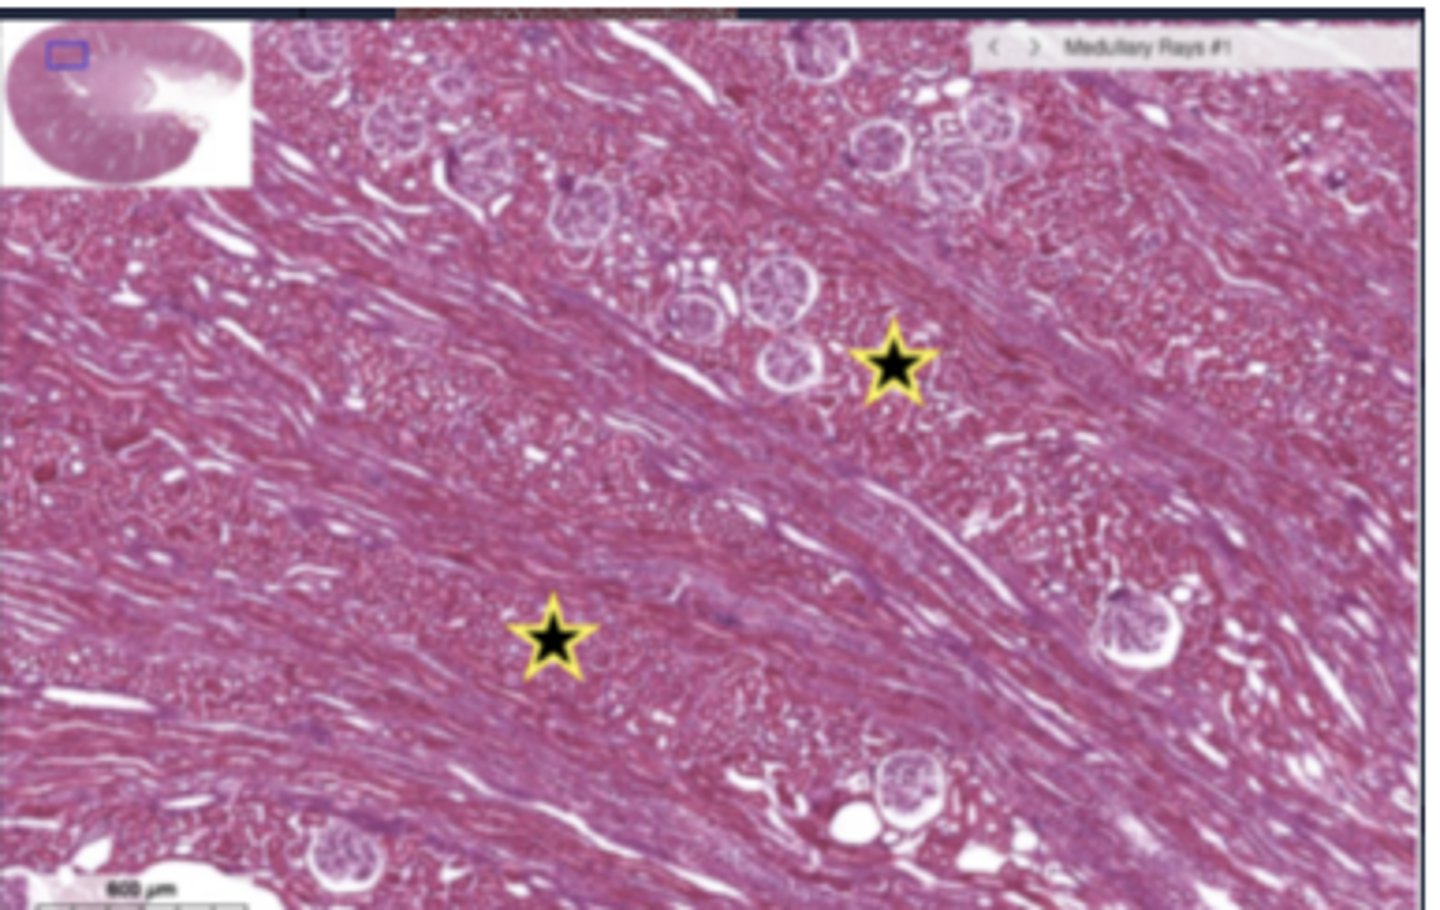

thin loop of henle

cortical labyrinth

X - proximal convoluted tubule